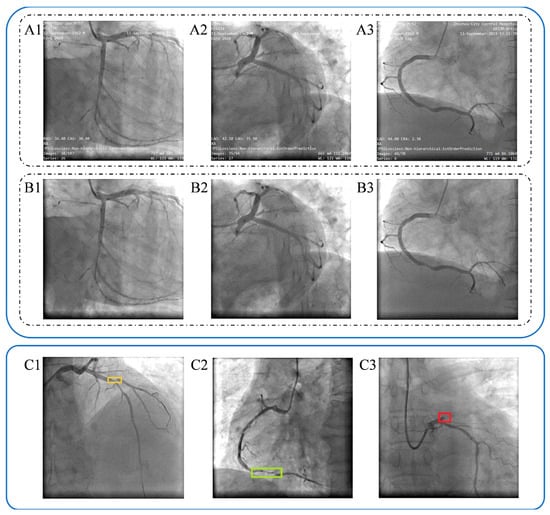

A total of 563 patients diagnosed with Acute Myocardial Infarction (AMI) were initially screened. Following the application of predefined exclusion criteria and subsequent accounting for patient loss to follow-up, a final cohort of 408 patients was included for comprehensive analysis. From this final cohort, 1273 distinct coronary angiography (CAG) images were compiled and integrated into the image analysis study. The detailed clinical characteristics and statistical outcomes regarding the follow-up incidence of Major Adverse Cardiovascular Events (MACEs) for this patient population have been previously reported [22]. To prepare the data for the deep learning model, all acquired CAG images underwent desensitization (removal of patient-identifying information) prior to lesion annotation. Coronary lesions were manually labeled, with a definition of significant stenosis established as a narrowing of the coronary artery diameter exceeding fifty percent (≥50). The final annotated images, illustrating the various lesion types, are presented in Figure 4.

Figure 4. Coronary angiography image desensitization and labelling. (A1A3). Original images of coronary angiography from patients. (B1B3). Desensitization of relative original images. (C1C3). Labelling of the narrowed coronary arteries image, dark yellow in (C1) presents limited meaningful lesion, light green in (C2) presents diffuse lesion, red in (C3) presents completely occlusive lesions.